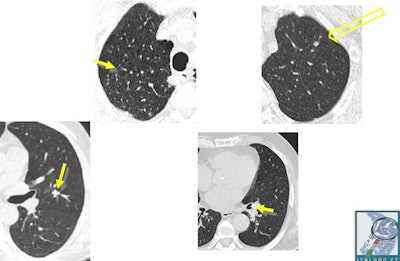

Smokers or ex-smokers, who smoked at least 20 pack years in the last 10 years, from Florence, Pisa, and Pistoia from the ages of 55 to 69 were randomized to receive an annual invitation for LDCT screening for four years (study group) or usual care (control group). All participants were followed up for vital status and cause of death at the end of 2014 and lung cancer incidence at the end of 2013.

After the nine-year follow-up, the study group included 1,613 participants with 67 lung cancer cases. The control group included 1,593 people with 71 lung cancer cases. Also, the researchers observed a greater proportion of stage I lung cancers in the study group (36% versus 11%). They estimated nonsignificant reductions of 17% for overall mortality and 30% for lung-cancer specific mortality in the study group.

The lung cancer incidence pattern in the ITALUNG trial confirmed the high sensitivity of low-dose CT screening and adds to the results of other LDCT trials. None of the previously published outcome studies, including the ITALUNG trial, has sufficient statistical power alone to detect a real benefit, the authors noted.